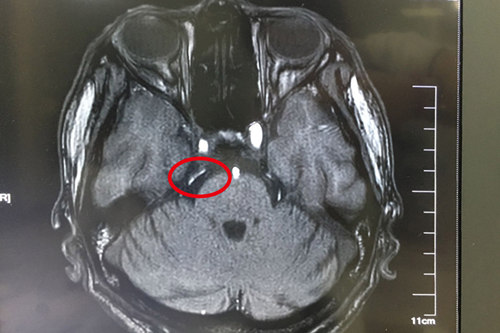

术前核磁共振显示:双侧三叉神经周围见小血管与之接触,并见骑跨

待做完各项检查之后,神经外科主任沈建康教授和科室其他医生一起讨论了王大爷的病情,排除了继发性三叉神经痛,一致认为患者现在发作频繁,吃药已无法控制病情,手术指征明显。待准备就绪后,8月1日下午,由沈教授亲自主刀,借助德国蔡司双荧光显微镜,王大爷的微血管减压术顺利完成;术后8天拆线,恢复良好,现已顺利出院。